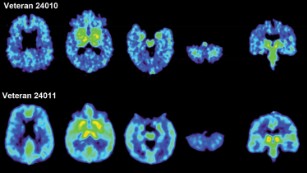

To try and understand the source of the changes, Goldstein and his colleagues mimicked the experiences of the human brains in mouse models, by exposing mice to repeated head trauma, like that in football, and single blast head trauma, similar to military combat.

The researchers found similar pathologies in both the mouse and human brains, regardless of the type of blast exposure they had experienced. Goldstein and his colleagues also measured the mice for concussion-like symptoms by testing their arousal and balance. They found that even without concussion, the mice exposed to the head trauma still exhibited changes in the brain.

Using animal models and computer modeling, Goldstein and his partners were able to see progression of the disease, finding that as tau built up, it began to work its way through the brain.